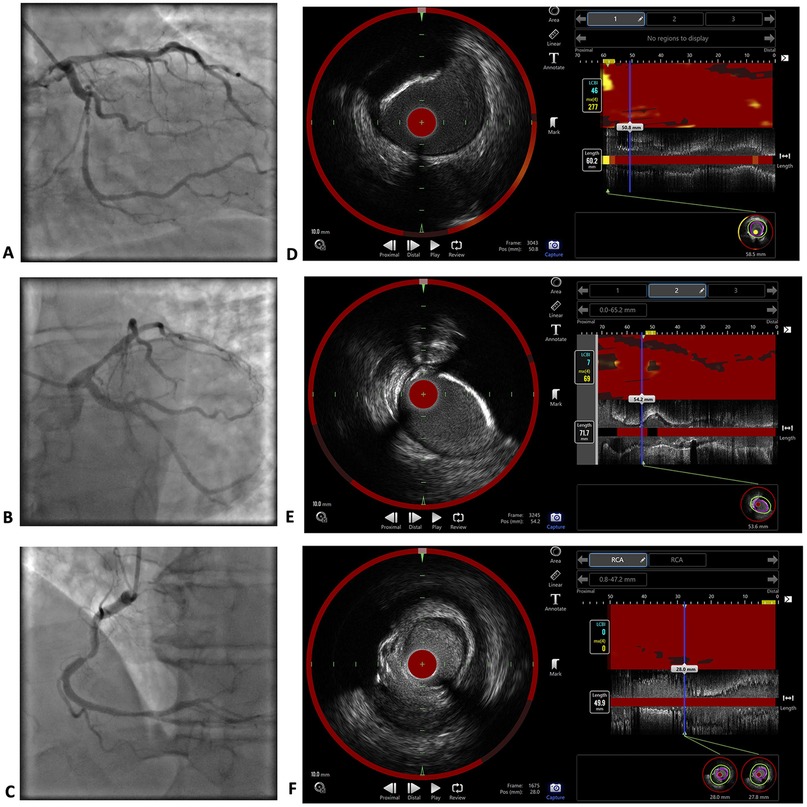

Background Elevated triglycerides have been established as a cardiovascular risk marker and the literature suggests an association with lipid-rich plaques. We report a case of severe hypertriglyceridaemia that did not result in lipid-rich atherosclerotic lesions. Case summary Coronary angiography of a 54-year-old man with a triglyceride level >113.00 mmol/Ll revealed severe multivessel disease. Near-infrared spectroscopy (NIRS) demonstrated a low plaque lipid content, including the maximum lipid-core burden index within 4 mm of 0 in the right coronary artery (RCA), with >90% stenosis in the middle segment. To achieve a rapid reduction in the triglyceride level, intravenous administration of insulin and heparin combined with subsequent plasmapheresis was used, and a triglyceride level of 5.79 mmol/Ll was achieved before discharge. Genetic testing confirmed familial hypertriglyceridaemia with a pathogenic variant in the lipoprotein lipase gene. Conclusions In a patient with severely elevated serum triglycerides and premature three-artery disease, low plaque lipid content was established with the NIRS investigation. Pharmacological management of very severe hypertriglyceridaemia with intravenous insulin and heparin therapy can rapidly decrease triglyceride levels.